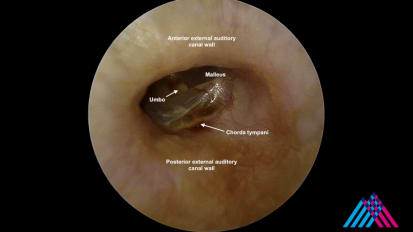

Mount Sinai head and neck surgeons perform a direct laryngoscopy with biopsy of the tongue base to confirm a diagnosis of squamous cell carcinomaMount Sinai Otolaryngology Surgical Series: Ear Drum Repair (Tympanoplasty) With Lateral Graft

Mount Sinai neurotologists perform a minimally invasive endoscopic approach to perform a lateral graft tympanoplastyMount Sinai Otolaryngology Surgical Series: Ear Tube Placement (Myringotomy)